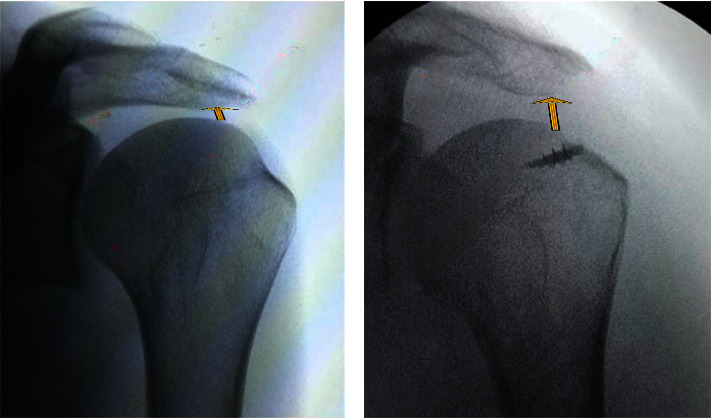

Abstract Image